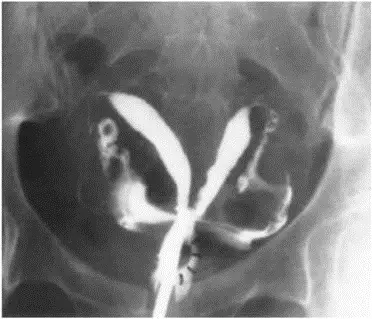

28 歲G3P0 的女性,因長期為經痛、經血過多( heavy menstrual bleeding )和性交疼痛所困擾,自述前三次懷孕都在 12 週內就自然流產,子宮輸卵管攝影( hysterosalpingography )影像如圖所示。建議接受子宮鏡(hysteroscope )中膈切除手術,下列何者是手術後最可能改善的情況?

圖中為子宮輸卵管攝影(hysterosalpingography, HSG)影像,顯示子宮腔內有一由子宮底向下延伸的充填缺損(filling defect),將子宮腔分為兩個近似對稱的半腔,整體呈現「心形(heart-shaped)」或「雙角形」外觀。雙側輸卵管管腔顯影,顯示輸卵管通暢(patent)。

HSG 所見之子宮底中央凹陷深度是鑑別**中膈子宮(septate uterus)與雙角子宮(bicornuate uterus)**的重要線索:

- 中膈子宮:外側子宮輪廓正常或輕微凹陷(< 1 cm),腔內有中膈向下延伸

- 雙角子宮:子宮底外側明顯凹陷(> 1 cm),形成兩個獨立子宮角

結合臨床病史(習慣性流產、子宮鏡中膈切除術的建議),本圖最符合**子宮中膈(septate uterus)**的 HSG 表現。確認診斷通常需合併 3D 超音波或 MRI 評估子宮外輪廓。